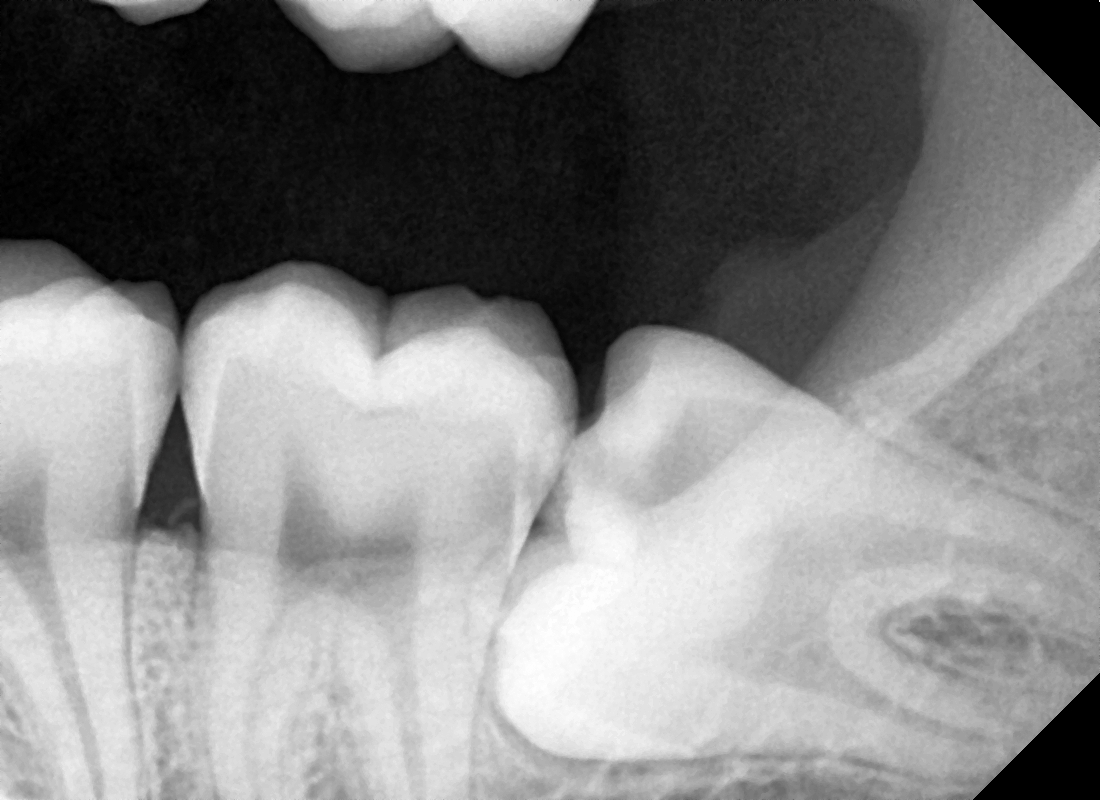

일단, 엑스레이를 보면

제가 빨간색으로 표기를 해 둔 ‘틈’ 이 있습니다.

근데, 이 틈이 거울이나

우리 눈으로 봤을 땐 틈이 없는 것 처럼 볼 수 있으나

실제로는 깊고 좁은 틈입니다.

즉, 여기서 음식 저류가 나타나게 될 텐데

양치질로 절대 닦아 낼 수 없는 곳입니다.

즉, 세균이 쉽게 번식이 되면서

광범위 충치들이 만들어질 수 밖에 없습니다.

아울러, 사진에서 볼 수 있는 것 처럼

치아의 치관이 조금이라도 맹출이 되어있다면

미리미리 발치를 하는 것 또한 도움이 될 수 있습니다.

예방 차원에서요^^